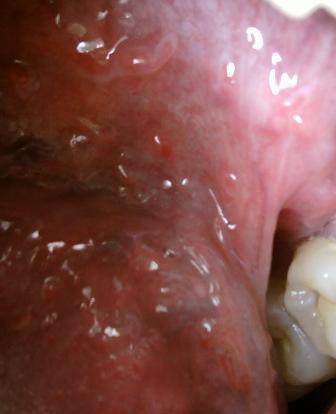

石家庄九州皮肤病医院 > 尖锐湿疣 > > > 尖锐湿疣病毒如何消灭尖锐湿疣病毒是一种人类乳头瘤病毒,这种病毒是比较顽固的,在治疗上有一定的难度,但是尖锐湿疣并不是不治之症,所以专家在此温馨提示:患病之后及时就诊,对于疾病的治疗和康复是很关键的,希望广大患者朋友们不要灰心。

尖锐湿疣病毒如何消灭只要经过正规的治疗,疾病是可以达到很好的治愈的目的的,希望广大患者朋友们应该认识到这一点,治愈尖锐湿疣的关键在于标本兼治,任何疾病只要经过正规的治疗,一定可以到很不错的治疗疾病的效果。临床上很多患者都是通过不良的性生活传染而发病的,所以避免发病的最好的方法就是要洁身自爱。尖锐湿疣是比较顽固的,关于其治疗费用是广大患者朋友们比较关心的一个问题。